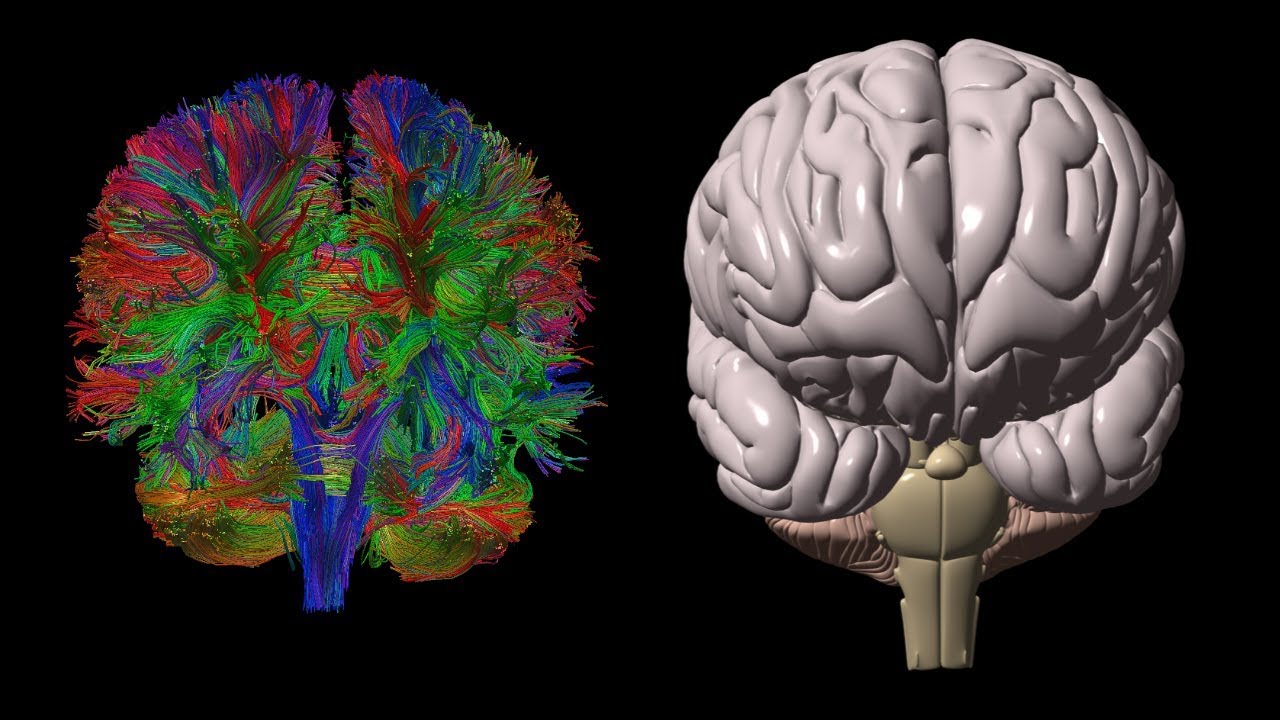

Diffusion Tensor Imaging (DTI) Explained

Diffusion tensor imaging - NeuRA Library

Diffusion Tensor Imaging 101 | Diffusion Imaging; Introduction

Diffusion Tensor Imaging (DTI)

Diffusion tensor imaging (DTI) tractograpy. The color-coding of

Diffusion Tensor Imaging (DTI) - Fiber Tracking - Imagilys

Diffusion Tensor Imaging (DTI) revealing connectivity in the brain

Using Diffusion Tensor Imaging (DTI), axonal fiber tractography

A) Diffusion tensor imaging (DTI)-based whole-brain tractogram in